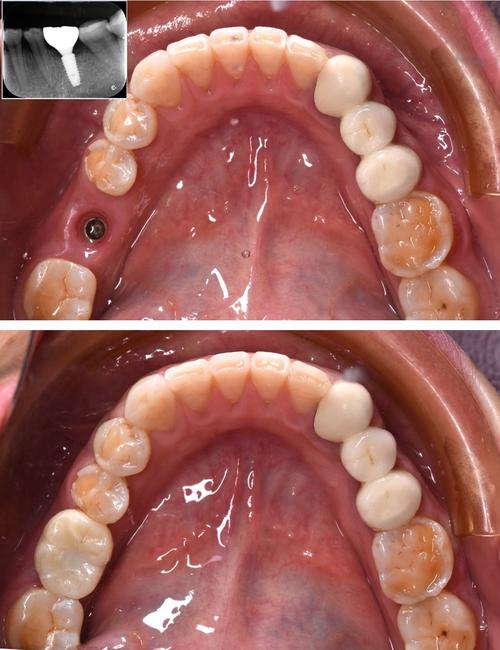

(图片来源网络,侵删)- 数字化种植:通过CBCT扫描和3D导板设计,实现种植位点、角度、深度的精准控制,创伤小、恢复快;

- 即刻种植:拔牙后立即植入种植体,缩短治疗周期(约3-4个月),适合牙槽骨条件良好者;